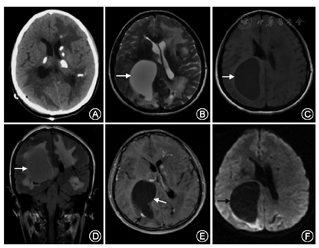

例1 患者女性,35岁,主因"发现颅内占位10年"于2015年5月19日来我院就诊。患者于10年前自觉左侧肢体无力,在当地医院查头颅CT及MRI提示:右颞顶巨大囊性占位,双侧基底节区多发钙化,于当地医院行颞顶占位切除术,术后分别在当地医院、首都医科大学宣武医院、首都医科大学附属北京天坛医院行病理学检查,结果未能明确病变性质,术后未再进行其他治疗,症状好转。5年前复查头颅MRI提示:右枕、左额、左枕分别出现长T1、长T2信号病变,双侧基底节区多钙化,仍无不适主诉,未进一步治疗。5个月前出现间断性周身乏力,复查头颅MRI提示:右枕部占位性病变明显增大,周围组织压迫明显,强化不明显。本次为手术入院。既往史:体健。无家族遗传史。神经科体检无阳性定位体征。眼底检查未见异常。头颅CT:双侧底节区可见钙化灶,双侧脑白质低密度灶。头颅MRI:左侧额叶、右顶叶可见多发囊状长T1、长T2信号,部分边缘可见结节样等T1、稍短T2信号,双侧基底节区可见散发点片状稍短T1、稍短T2信号,周边可见大片稍长T1、稍长T2信号,DWI见囊内稍受限信号,增强扫描可见多发结节样、条状及环形强化(图1)。右侧侧脑室受压,中线结构向左侧移位。病理检查:血管瘤样增生,可见充血、出血,血管间隙可见含铁血红素;血管变性充血,周围可见铁环(图2)。